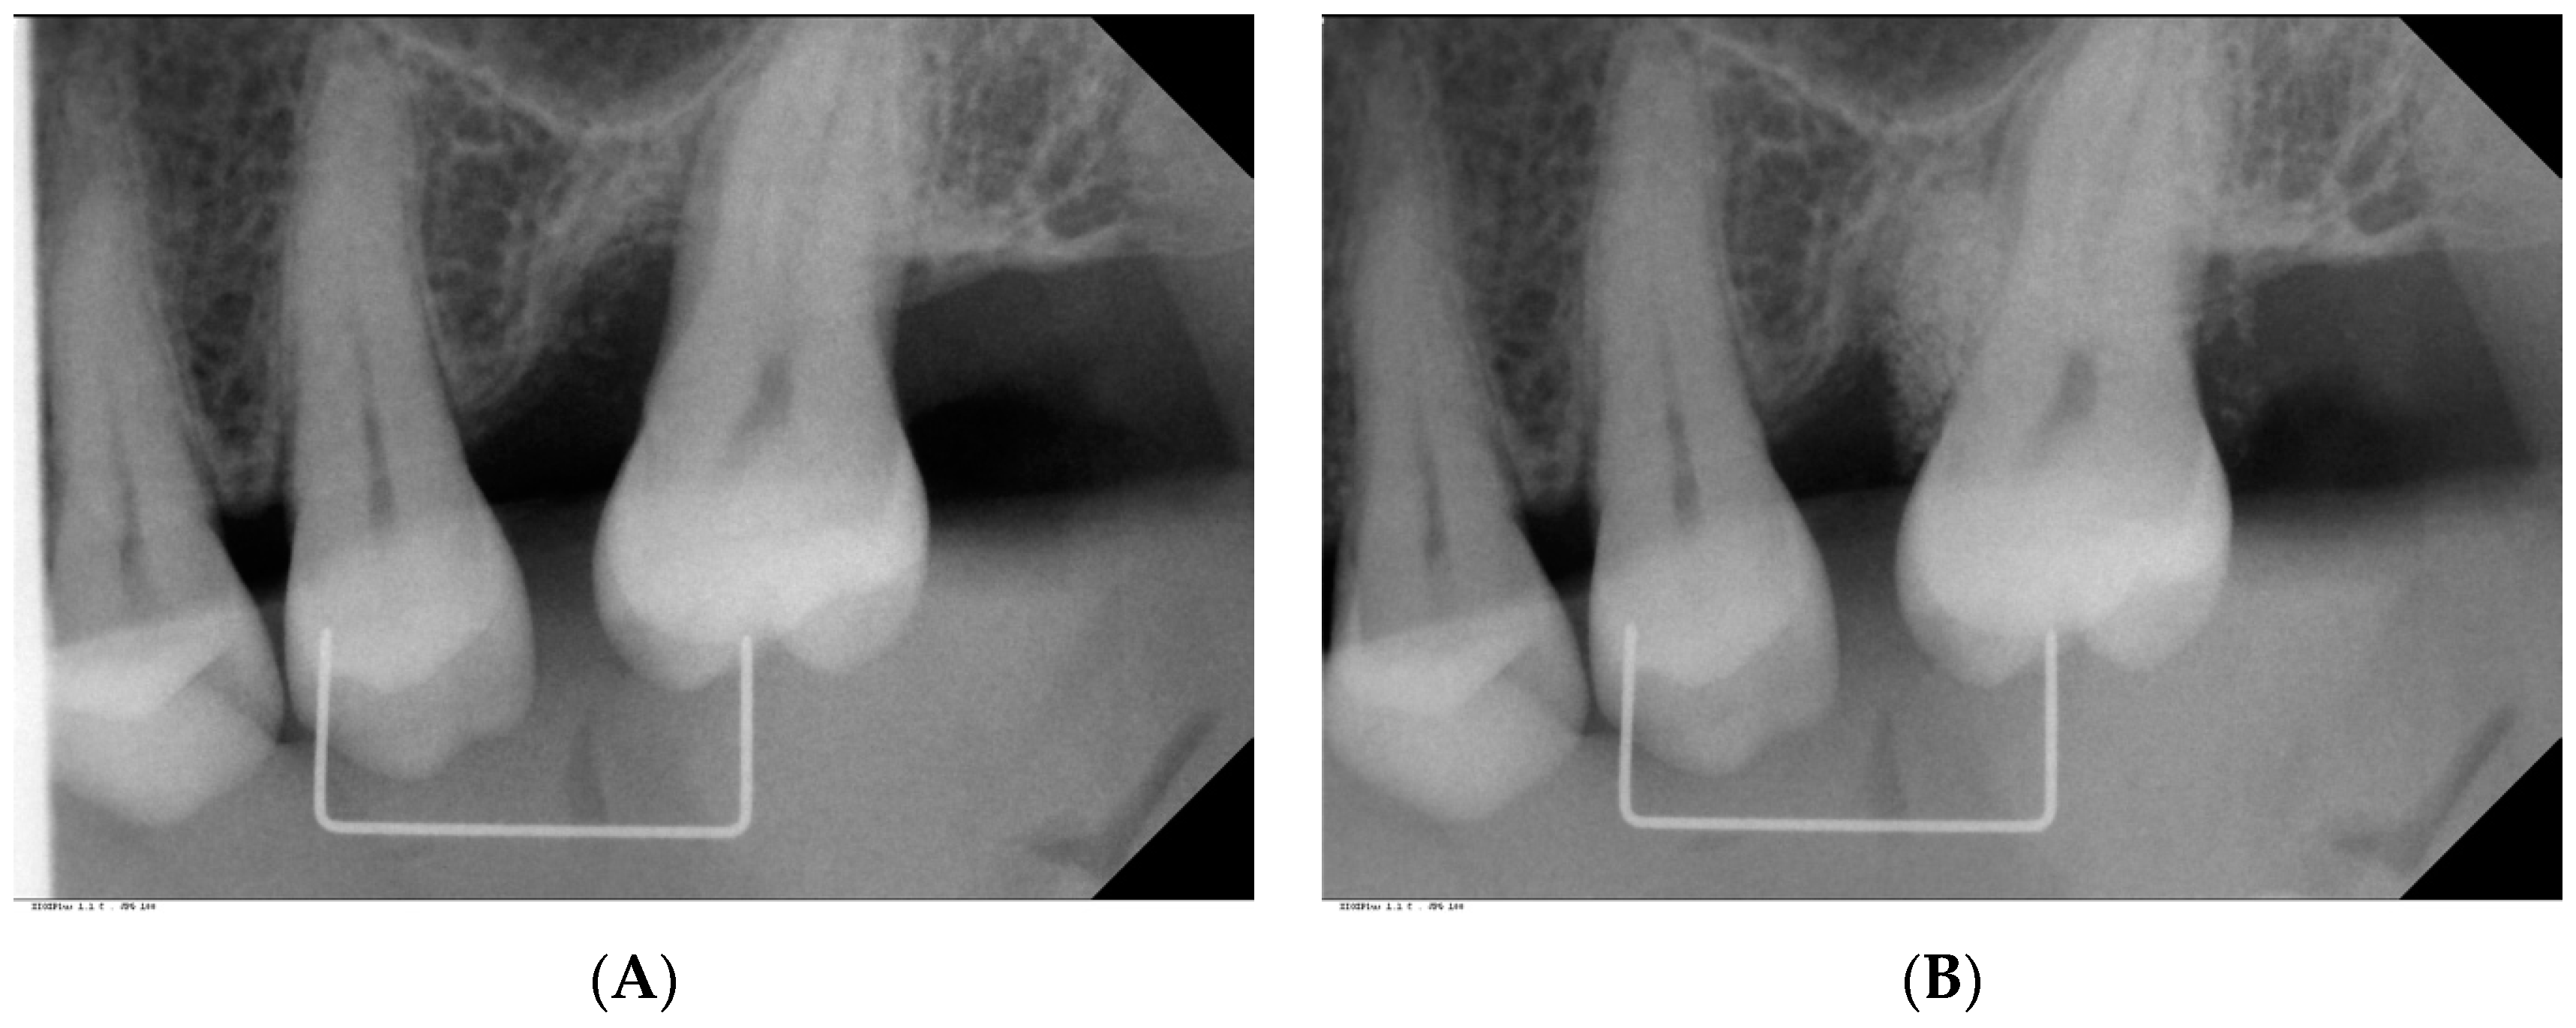

| Radiographic defect depth (mm, median, IQ) Min/max | 6 (5, 7) 3, 9 | 0 | <0.001 |